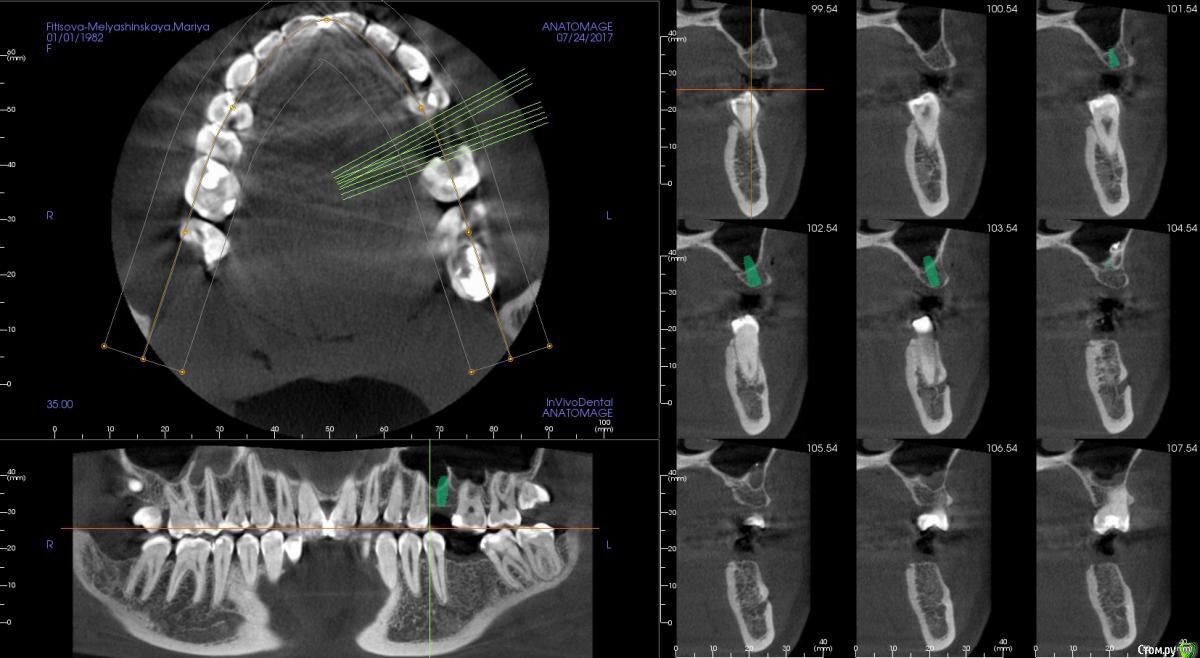

kamranchick Опубликовано 24 июля, 2017 Поделиться Опубликовано 24 июля, 2017 Ребятулечки, а можно тут как то поставить имплантат, без инвазии?В принципето молоток приветствуется если он тут сработает и сработает ли.хочу поставить 3.5 на 8.5 Ссылка на комментарий

kamranchick Опубликовано 24 июля, 2017 Автор Поделиться Опубликовано 24 июля, 2017 Сработает. Комп рисует без 1,5-2 мм, так что очень даже. Апикально кость с фрезы прям в перегонку стукнуть?))) Ссылка на комментарий